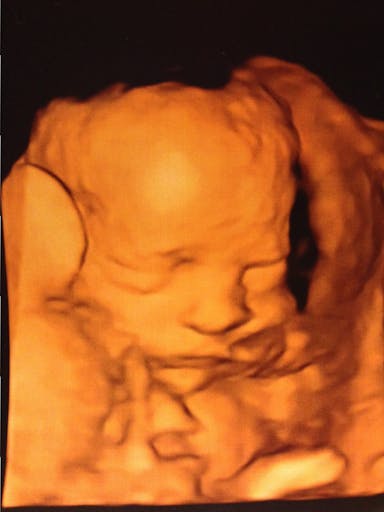

Apparently abortion advocates can’t even admit that a preborn baby who could survive outside the womb on her own is a child (or, in one case even a human life). Colorado’s legislative session has brought a number of debates on abortion-related topics, and at least two of the hearings, Representative Gordon Klingenschmitt has held up a 3D ultrasound photo of a 28-week-old baby and asked abortion supporters to tell him whether she is an unborn child. This baby is Lydia Neville, the daughter of another state representative, Patrick Neville.

Fewer still can see a photo of a baby who could survive outside the womb with a near absolute certainty – like Lydia Neville – and claim she is not a child yet. (Fetal viability continues to move up, and the earliest known babies to survive with modern medicine were born at 21 weeks and 5 days and 21 weeks and 6 days. More info on viability is available here.)

Lydia covers her face with her hand and kicks up her feet.

Lydia’s ultrasound photo demonstrates the lengths to which abortion advocates are willing to go to deny the humanity of children. In order to exalt abortion to an untouchable pedestal, an unquestionably alive human child is not even a child until she literally passes through the birth canal. Until that point, she is merely “potential life” that can be taken at will.

“Potential life” at 28 weeks.